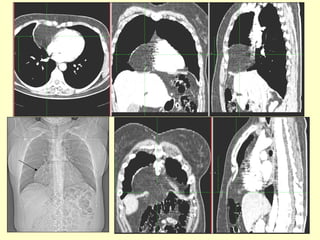

1. Radiografie PA: imagine opacă , aerică, mixtă în

funcţie de organul herniat

2. Radiografia de profil

3. Examen cu substanţă de contrast al tubului

digestiv (pentru organe herniate cu lumen)

4. Computer-tomografie - foarte importante sunt

reconstrucţiile multiplanare în plan sagital şi

coronal pentru aprecierea defectului diafragmatic

imaginea localizată la baza

hemitoracelui stâng în unghiul

costodiafragmatic posterior care

determina ascensiunea;

hemidiafragmului stâng este data

de o herniere de grăsime;

retroperitoneală (perirenală) şi de

asemenea de pol renal stâng

superior –hernie Bochdalek;

Hernia Bochdalek